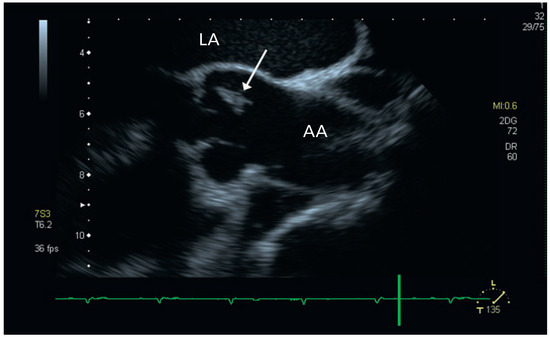

Aortic Valve Rupture Due to a Motorcycle Accident

by Daniela Vocke, Igal Moarof, Peter Matt and Pablo Anabitarte

Cardiovasc. Med. 2011, 14(6), 192; https://doi.org/10.4414/cvm.2011.01597 - 29 Jun 2011

Viewed by 93

Abstract

A 62-year-old male patient was admitted as a result of a motorcycle accident [...] Full article